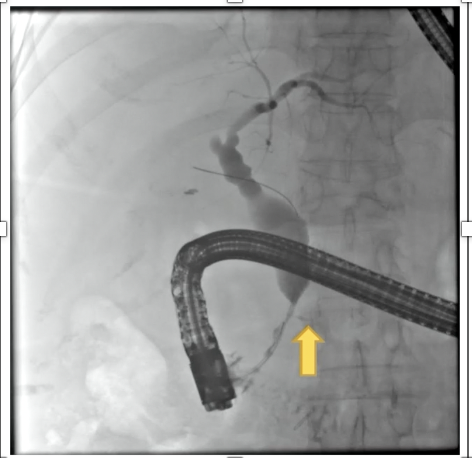

A

Aortoentertic fistula